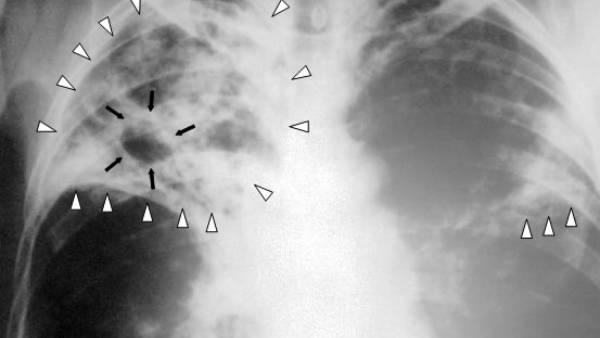

மாஸ்க் அணிவது, கைகளை அடிக்கடி கழுவி சுத்தமாக வைத்துக் கொள்வது போன்ற நடவடிக்கைகள் மூலம் மற்ற சுவாசப் பிரச்சினைகள் பெருவாரியாகக் குறைந்துள்ளன. ஆனால் மற்ற நோய்களுடன் ஒப்பிடுகையில் காசநோய் பாதிப்பு கம்கியான அளவே குறைந்துள்ளதாக மருத்துவர்கள் தெரிவிக்கின்றனர். காசநோயை ஏற்படுத்தும் பாக்டீரியாக்கள் மனிதனின் உடலில் இன்ஆக்டிவாக பல காலம் இருக்கும் என்பதால், காசநோய் பரவலைக் கட்டுப்படுத்துவது மிகவும் சிரமமான ஒன்று.

எய்ட்ஸ் அல்லது இதுபோன்ற மோசமான சில பாதிப்புகளைக் கொண்டிருப்பவர்களின் உடல்களில் நோய் எதிர்ப்புச் சக்தி குறைந்துவிடும். இதன் மூலம் அவர்களுக்கு மிக எளிதாகக் காசநோய் போன்ற பாதிப்புகள் எளிதில் ஏற்படுவதற்கான வாய்ப்புகள் அதிகம். இதுபோல எளிதாகக் காசநோயால் பாதிக்கப்படும் ஆபத்து உள்ளவர்களையே முதலில் கண்டறிய மத்திய அரசு நடவடிக்கை எடுத்து வருகிறது. ஏனென்றால், இதுபோல காசநோய் பாதிப்பு தங்கள் உள்ளது என்பதே தெரியாமல் இருக்கும் நபர்கள் மூலமே நோய் எளிதாக மற்றவர்களுக்குப் பரவுகிறது.